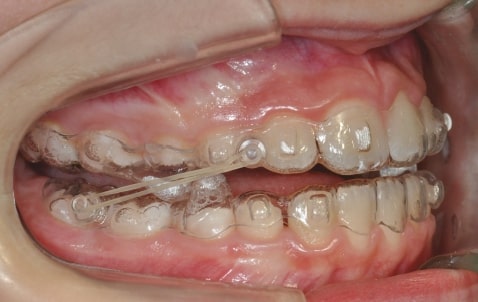

- Mandibular Advancement (A6 protocol) + angelBuon for Class 2 Elastics (Night Time)

Treatment details

AngelAligner KiD 1 (aligners changed every 10 days)

- Class 1 both sides

- Overjet/Overbite Correction

Treatment progress